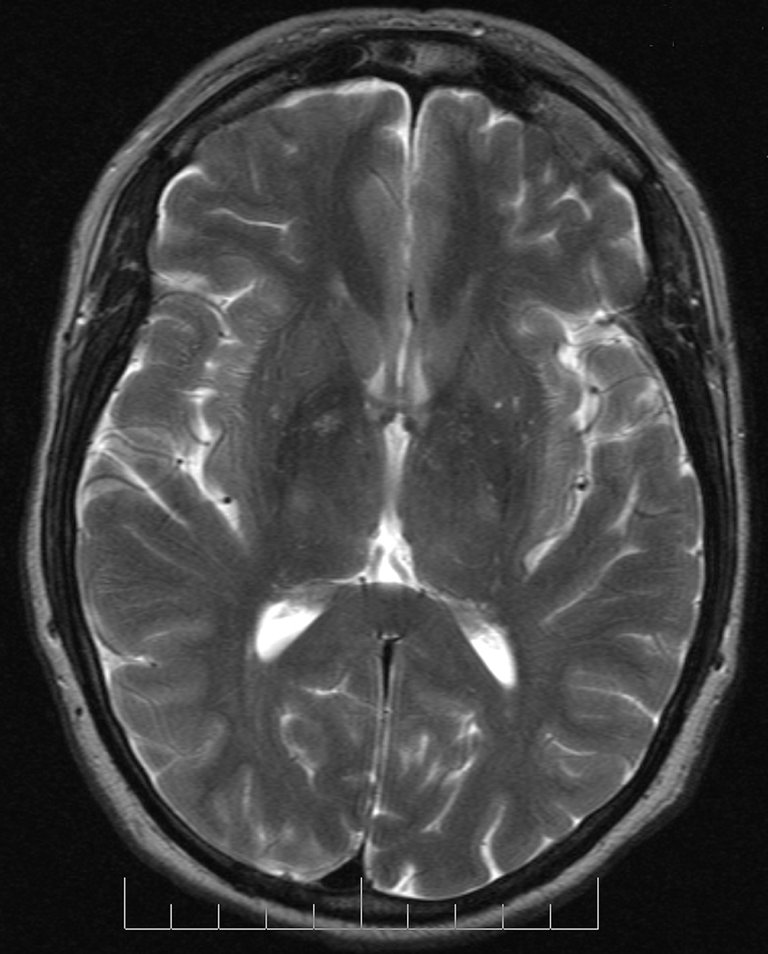

Investigadores de Biodonostia OII e médicos do Hospital Universitario Donostia identificaron conxuntamente un xene crave nos cancros cerebrais malignos e á vez máis frecuentes (SOX1), segundo anunciaron na revista Scientific Reports.

De feito, SOX1 é un factor de transcrición. A célula nai está relacionada co mantemento dos adultos e frecuentemente está silenciada en cancro, xa que exerce una función defensiva nas células tumorales. É dicir, actúa como un tumor eliminador en varios cancros sólidos. Pero o equipo de investigación coordinado por Ander Matheu detectou un alto nivel de SOX1 na biopsia de certos tumores que causan una baixa supervivencia nos pacientes. Así mesmo, identificouse un aumento significativo dos niveis de SOX1 nunha poboación específica de células tumorales responsables da formación e progresión do glioblastoma.

Cando os investigadores silenciaron o SOX1 nas células de glioma, detectan que estas perden todas as súas propiedades malignas, incluíndo a capacidade de autoinnovación e a actividade tumoral.Por iso, concluíron que o xene desempeña una función oncogénica neste tipo de cancro. Os resultados do traballo permitiron aos investigadores de Biodonostia OII identificar estratexias innovadoras e propoñen utilizar o xene como finalidade terapéutica e como biomarcador de estratificación.